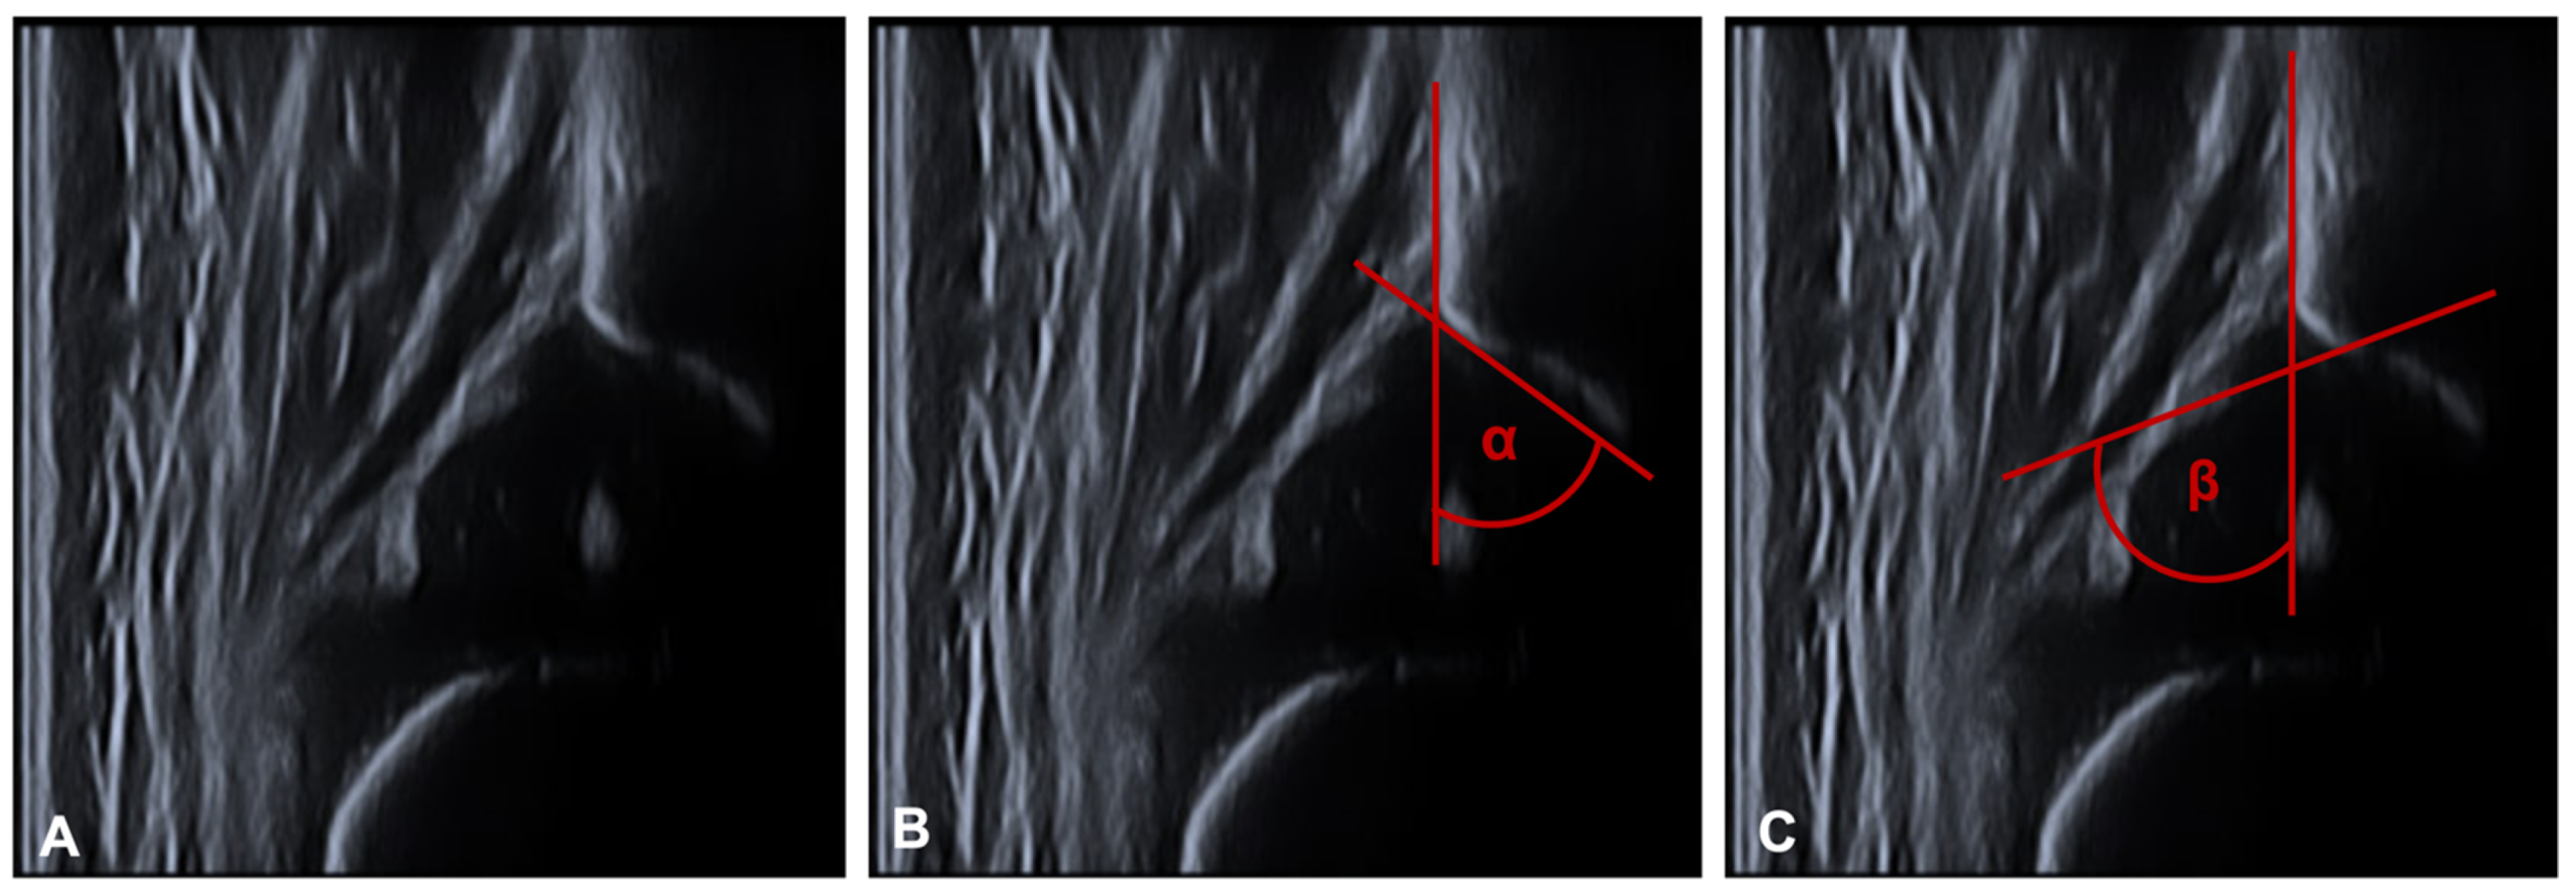

3.1. Sonographic Evaluation

| alpha | In total | 52.2 | 9.8 | 65.6 | 3.3 |

| female | 52.2 | 9.6 | 65.7 | 3.4 | |

| male | 51.8 | 11.4 | 64.5 | 1.8 | |

| beta | In total | 74.2 | 9.3 | 63.9 | 6.8 |

| female | 74.0 | 9.9 | 64.0 | 7.0 | |

| male | 75.1 | 7.9 | 63.7 | 5.8 |